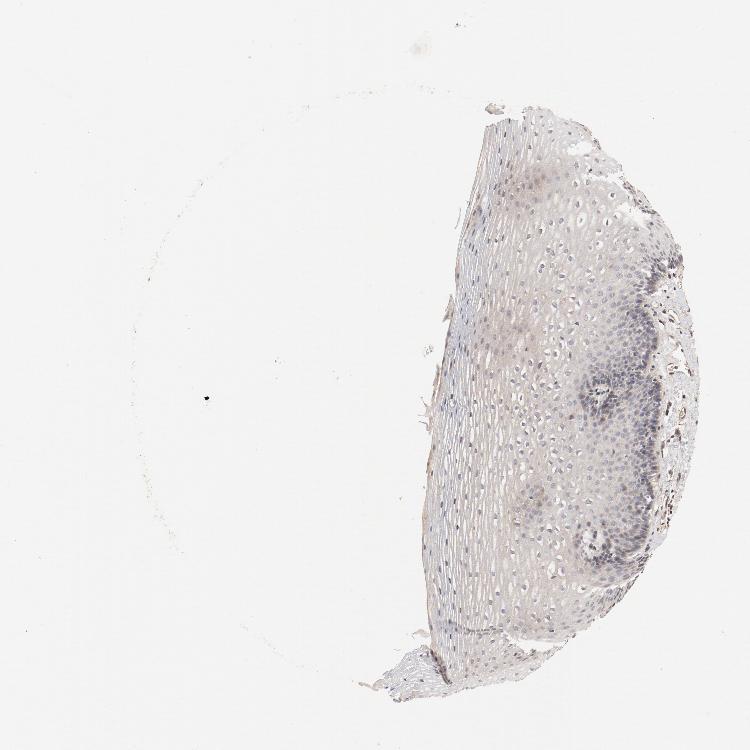

ESOPHAGUS - Antibody stainingi

Antibody staining in the annotated cell types in the current human tissue is reported as not detected, low, medium, or high, based on conventional immunohistochemistry profiling in selected tissues. This score is based on the combination of the staining intensity and fraction of stained cells.

Each image is clickable and will lead to virtual microscopy that enables deeper exploration of all samples and also displays staining intensity scores, fraction scores and subcellular localization as well as patient and tissue information for each sample.

Antibody HPA003539Antibody CAB018374

Squamous epithelial cells LowHigh